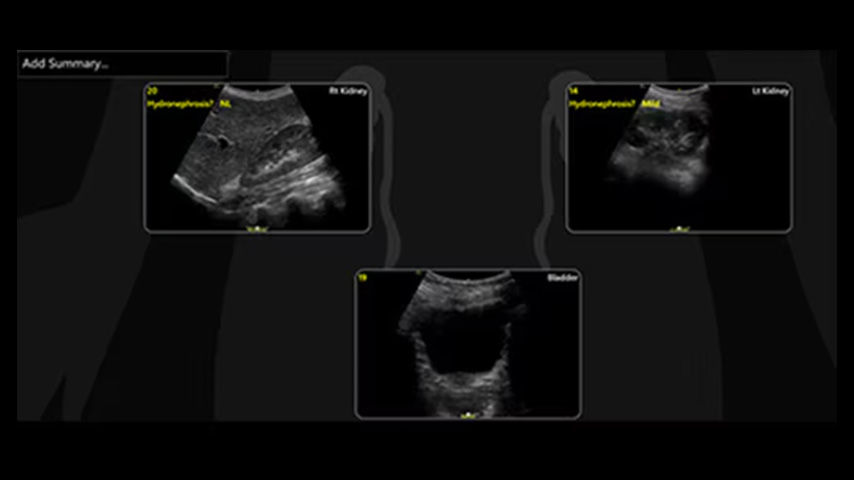

Quickly assess kidneys and the bladder with Renal Diagram

Simplify documentation and provide easy follow up for patients with suspected hydronephrosis. No need to type findings; simply assign a label from a pre-populated list that correlates with images.